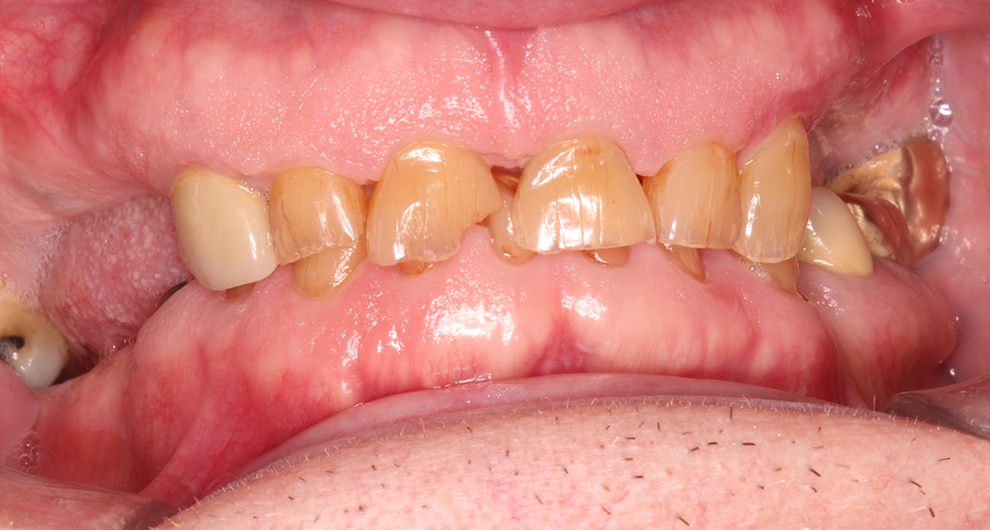

Click and drag the lines to reveal before and after

Before treatment After treatment

Before treatment

After treatment